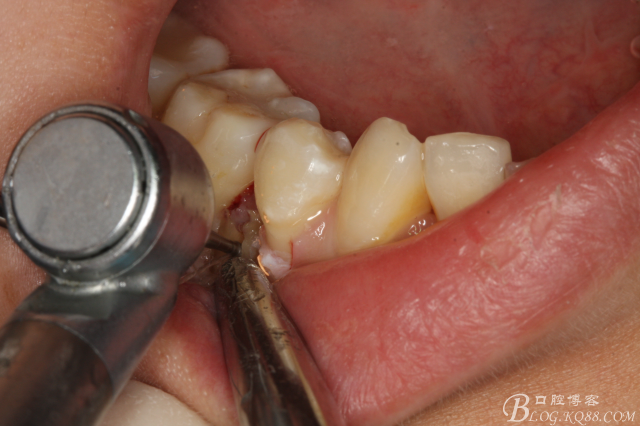

圖10.高速裂鉆垂直分根

圖11.形成牙根中央一個約5mm長、2mm寬溝槽。